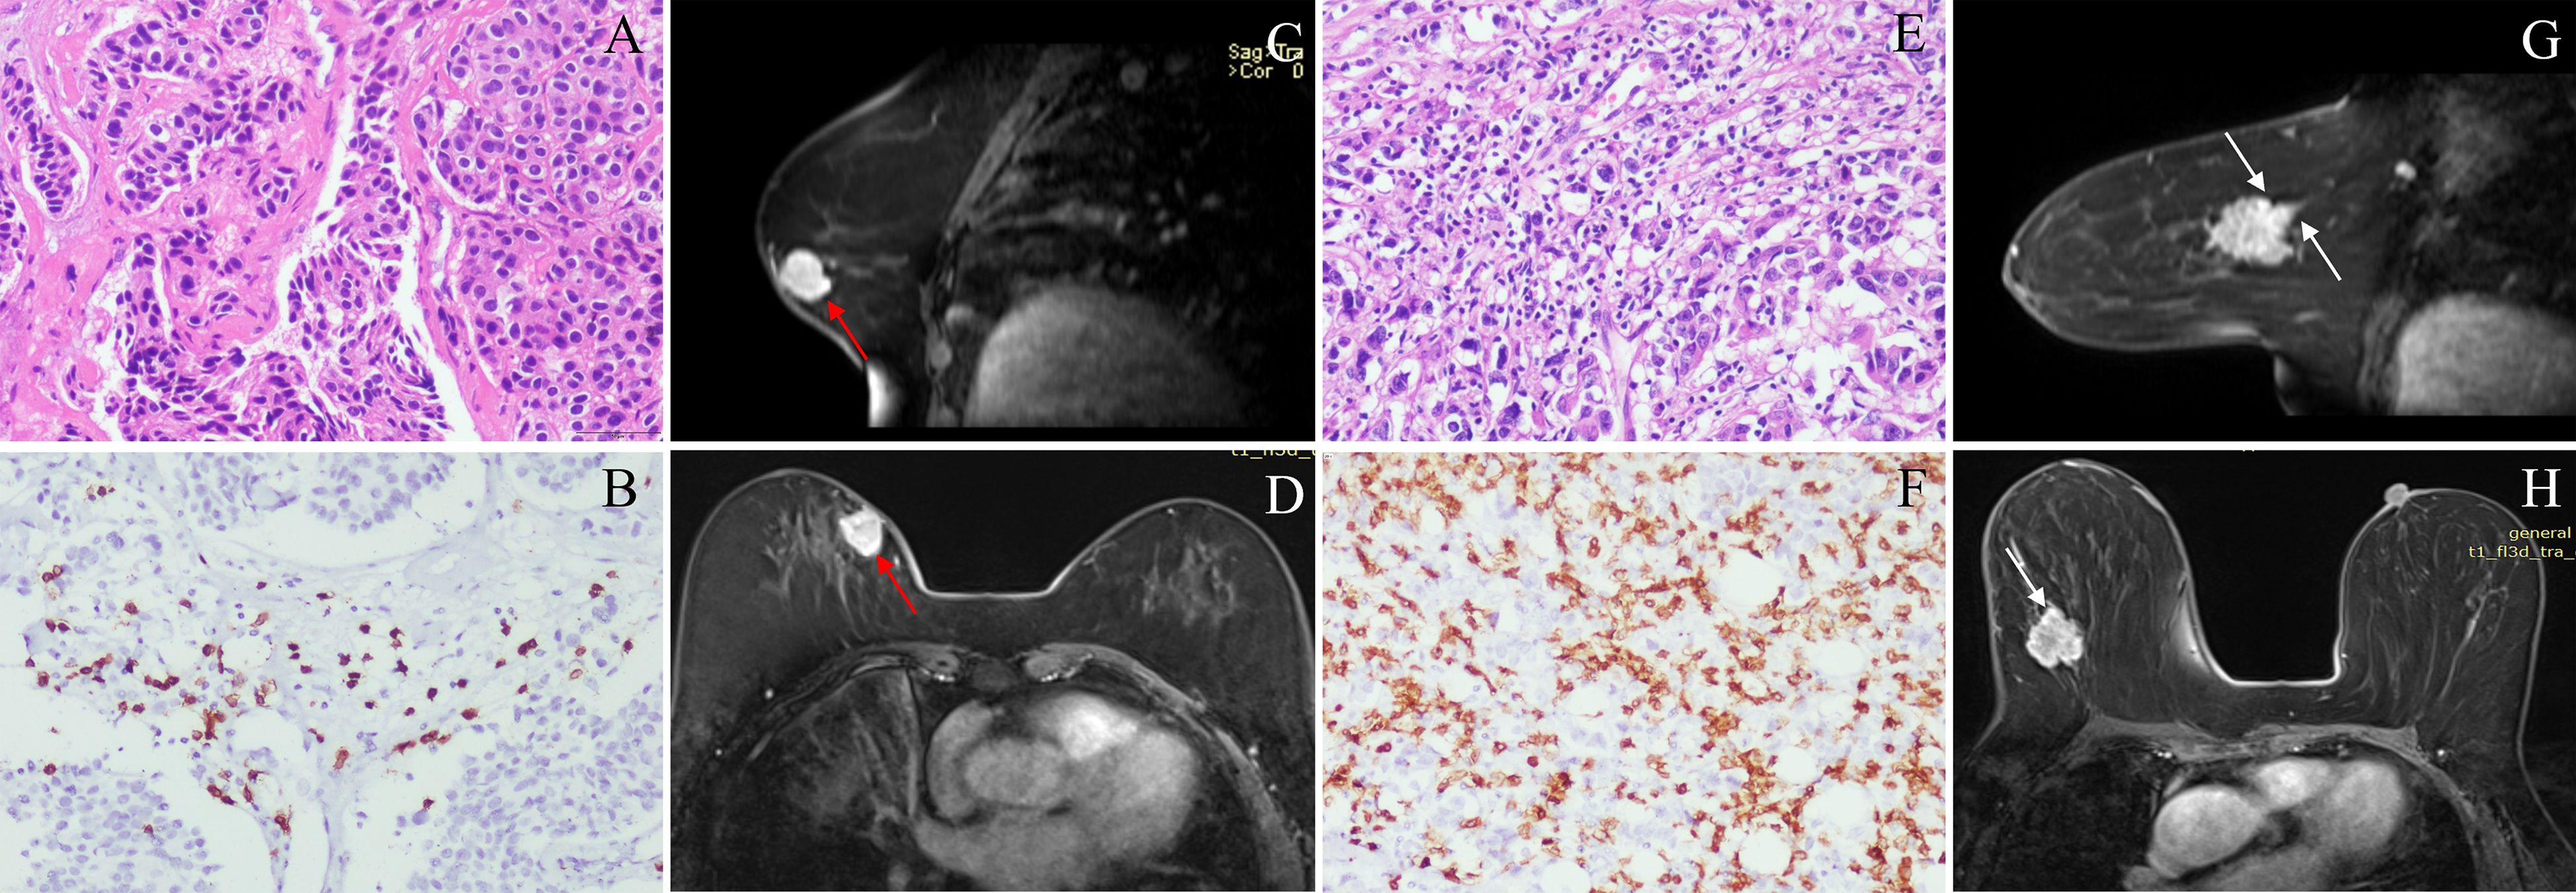

52.4% of patients (66/126) were low CD8+TILs level and 47.6% (60/126) were high CD8+TILs level. BC patients’ clinical and imaging features in the training and validation cohorts were shown in Tables 1 and 2. Among these features, there were significant differences in N stage, maximum diameter, tumor margin, and enhancement pattern in the training and validation cohorts, and T stage in the training cohort (p < 0.05). Classic MRI features of HER2-positive BC with low and high CD8+TILs levels were shown in Figure 2 and Figure 3. In the training cohort, univariate analysis showed significant associations between several risk factors and CD8+TILs levels, including T stage, N stage, maximum diameter, tumor margin, and enhancement pattern (p < 0.05). Multivariate regression analysis revealed that tumor margin and enhancement pattern were independent risk factors (p < 0.05). The AUC of the clinical-imaging model constructed by these two variables was 0.785 [95% confidence interval (CI): 0.690-0.881] and 0.803 (95% CI: 0.654-0.951) in the training and validation cohorts, respectively.

Figure 2. Classic MRI features of breast cancers with low and high CD8+TILs levels. A HER2-positive breast cancer ((A) HE ×200) with low CD8+TILs level (about 20%) ((B) IHC×200) presented an oval mass with circumscribed margin (red arrow) and homogeneous enhancement on DCE-MRI (C, D). A HER2-positive breast cancer ((E) HE ×200) with high CD8+TILs level (about 80%) ((F) IHC×200) presented an oval mass with not circumscribed margin (white arrow) and heterogeneous enhancement on DCE-MRI (G, H). MRI, magnetic resonance imaging; TILs, Tumor-infiltrating lymphocytes; HER2, human epidermal growth factor receptor 2; HE, hematoxylin and eosin staining; IHC, immunohistochemical; DCE-MRI: dynamic contrast-enhanced magnetic resonance imaging.